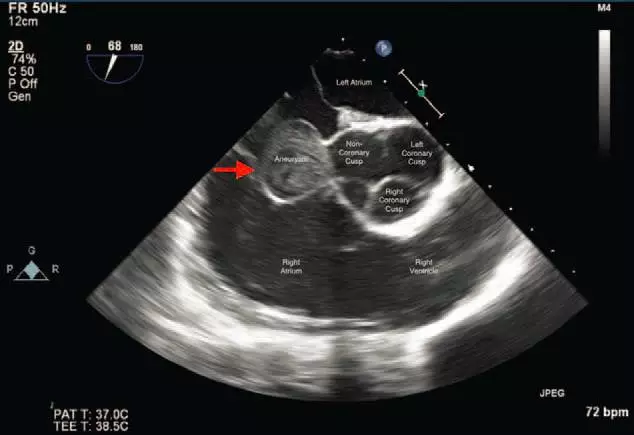

图示患者心脏超声检查结果

术中行经食管超声心动图以进一步评估肿瘤情况,结果发现,主动脉瓣非冠状尖呈明显外翻,边缘清晰,伴主动脉根增厚(真性动脉瘤),彩色多普勒超声进一步发现未破裂的瓦氏窦动脉瘤,在心脏舒张期呈自发性回声漩涡。